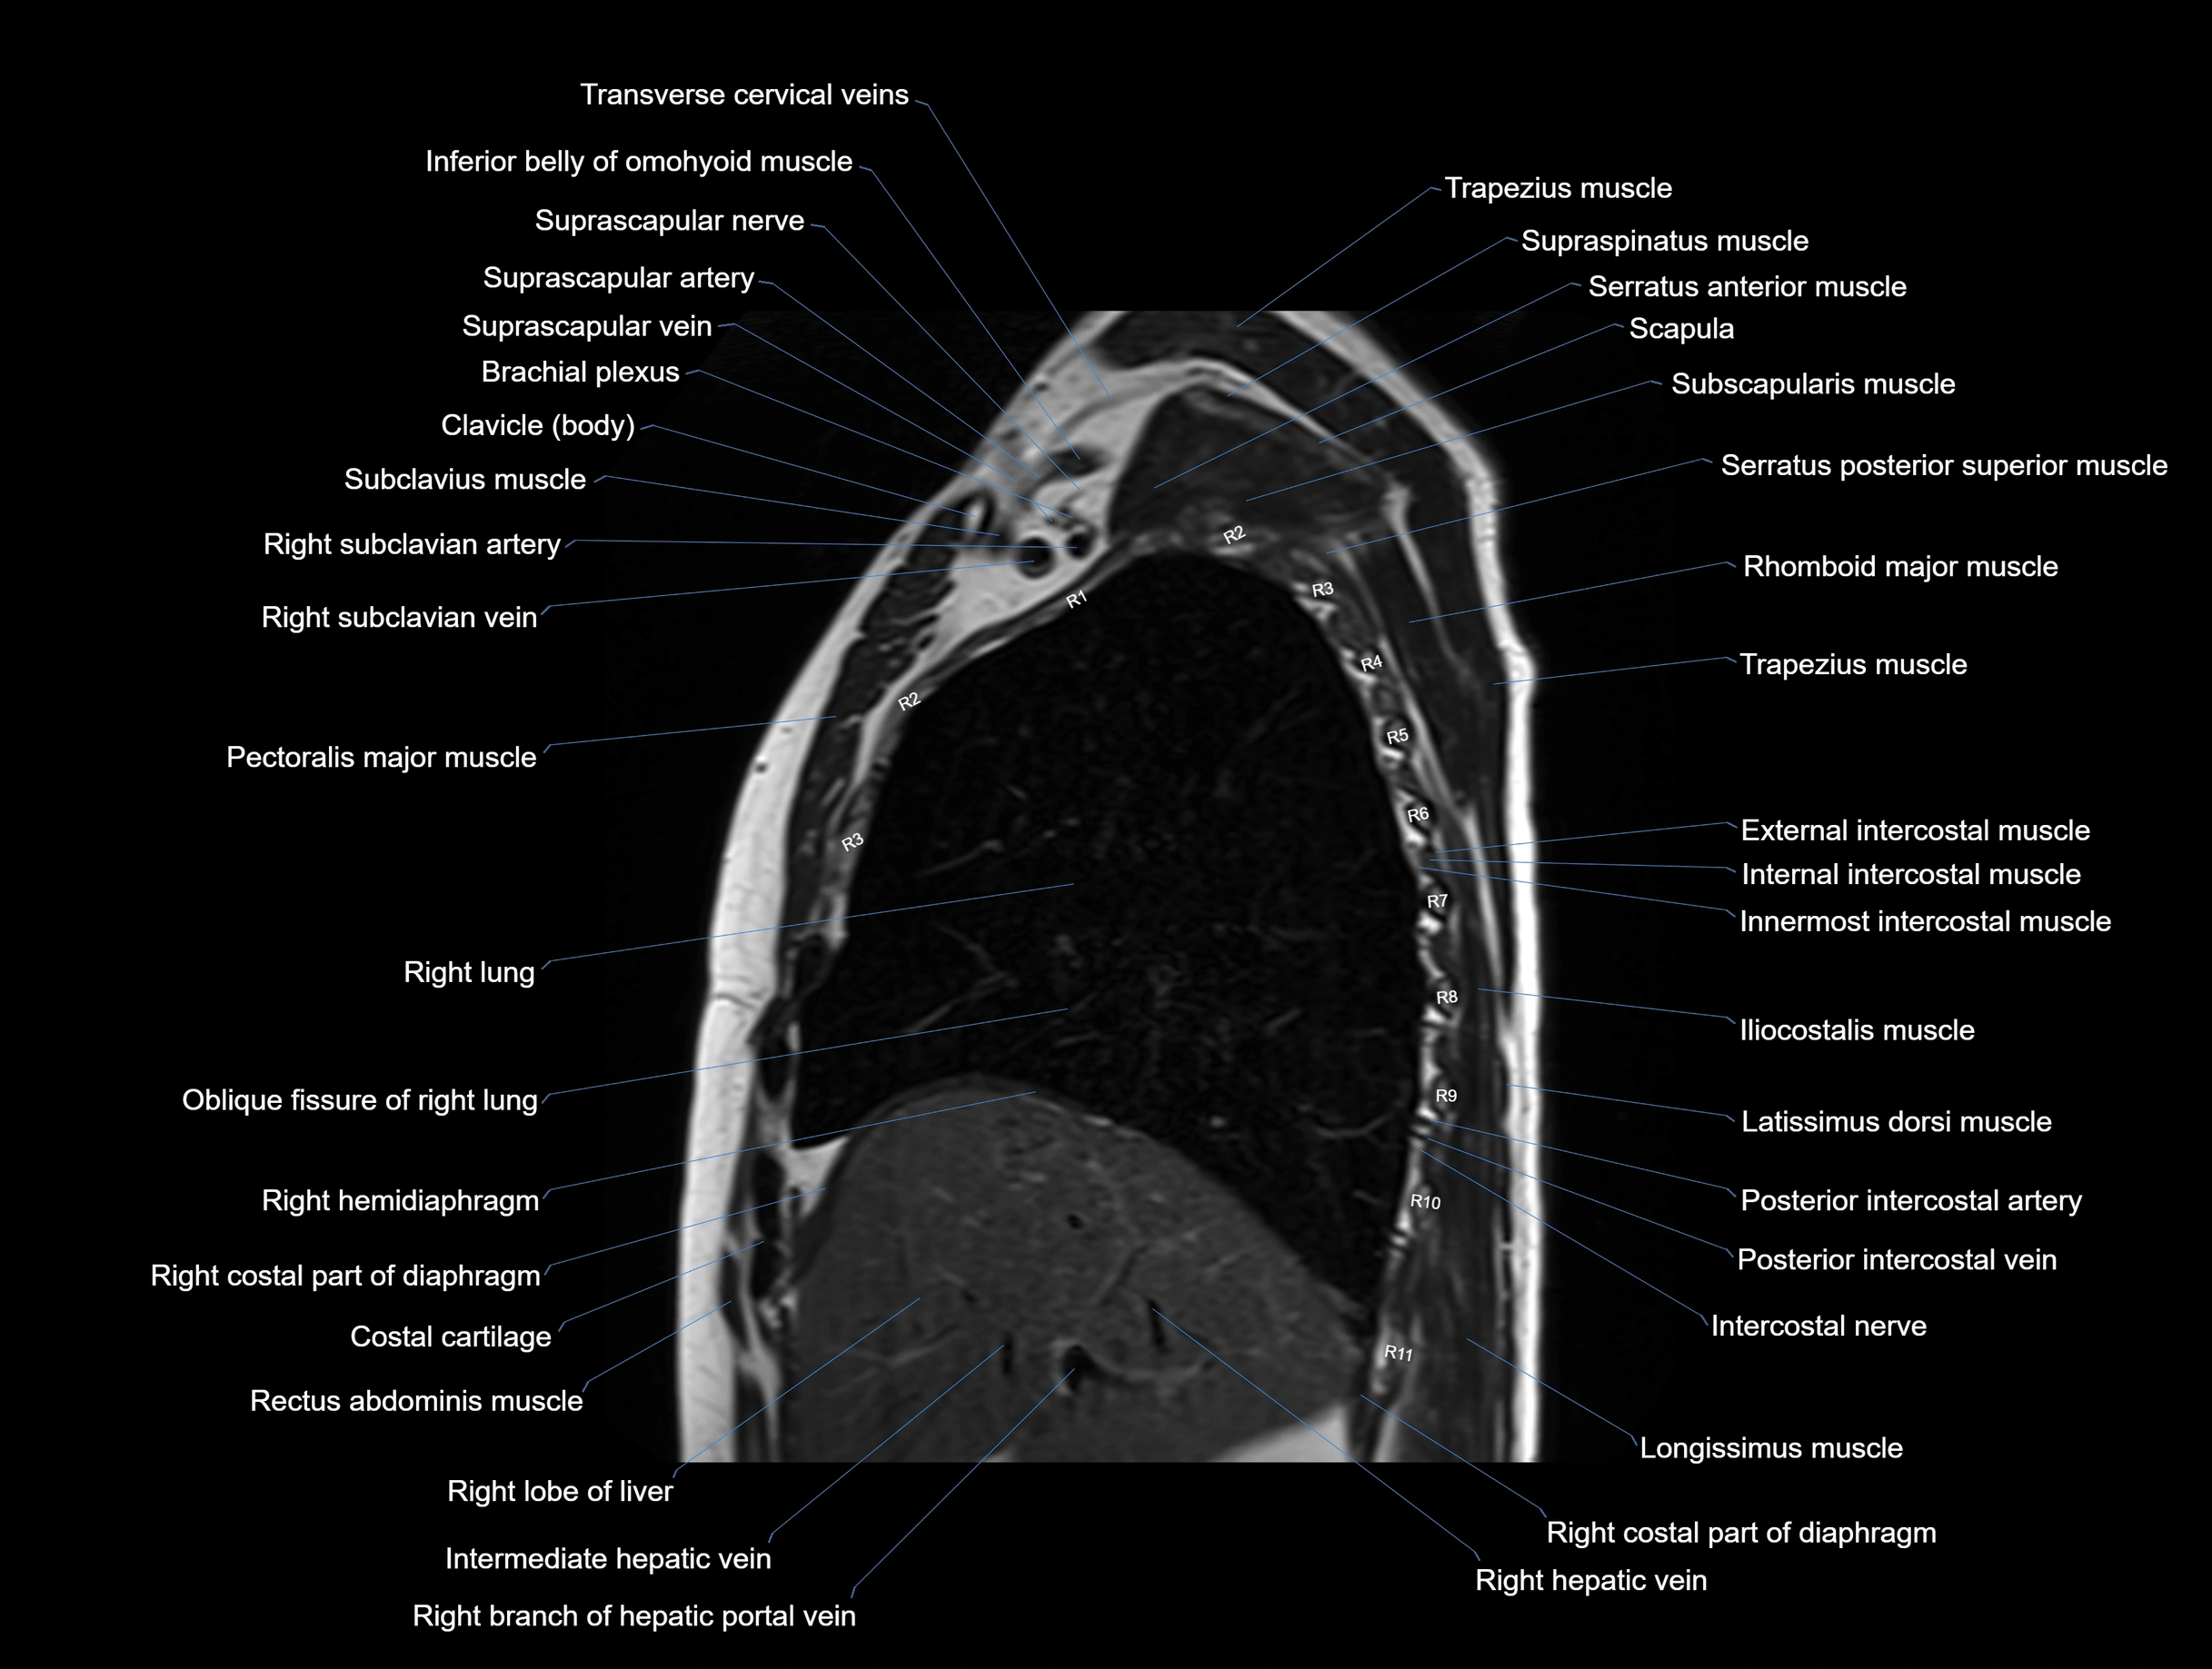

MRI images